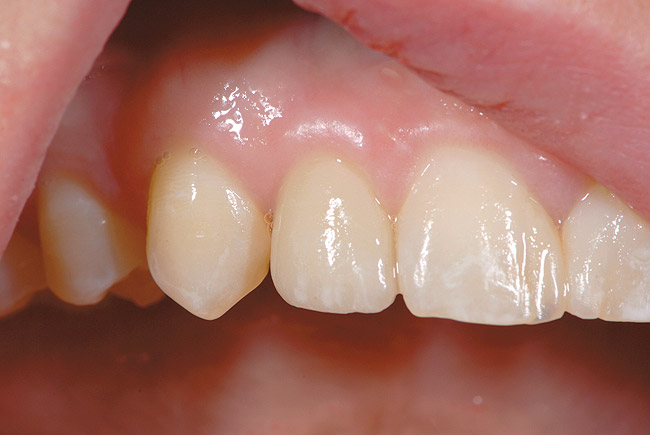

Figure 16  Replacement of the maxillary lateral incisor with a CAD/CAM zirconium abutment and a zirconium/ceramic crown.

Figure 16

Other factors may play a role in the final esthetic outcome. Indexing the position of the implant at the time of placement, use of provisional restorations, and customized impression copings to record gingival contours for laboratory fabrication of the abutment and crown are examples of techniques to enhance the overall esthetic result (Figure 13 through Figure 16). In addition, newer materials have been introduced to aid the fabrication of esthetic abutments and restorations placed on dental implants. Zirconium, both as an abutment and restoration, has been shown to have a beneficial esthetic effect and is well tolerated by the surrounding tissue.28 Caution, though, must be emphasized in the use of this material because it is not fully known how it will withstand functional loads long term, especially in the posterior areas. Titanium abutments remain the material of choice in the posterior areas.29 Waxing and casting of premachined UCLA-type abutments also offers an option for abutment design, enabling precise angle corrections when necessary, although the rise in the cost of precious metals may limit the use of this material in the future. The significant improvement of abutments generated with computer-aided design and computer-aided manufacturing (CAD/CAM) has greatly enhanced the abutment design and fabrication. Metal ceramic restorations provide suitable restorations in the posterior region and are used because of their proven long-term success,1-3 although proper metal coping design is necessary for strength of the veneered porcelain. Gold occlusal surfaces, especially in the molar region, may be the best choice if the patient has high occlusal forces or parafunctional habits that may make material fracture a concern.